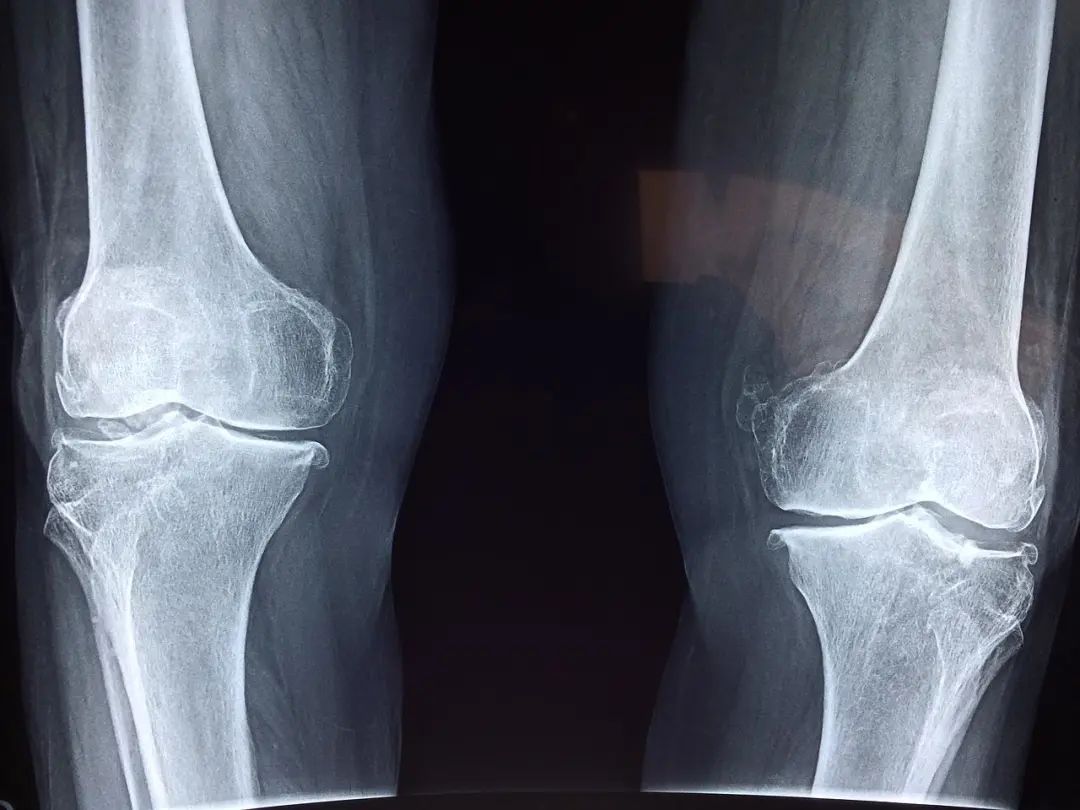

政策回顾:意向采购量为人工全髋关节约30.6万套、人工全膝关节约23.2万套,共54万套,占全国医疗机构总需求量的90%。按2020年采购价计算,公立医疗机构人工髋、膝关节采购金额约200亿元,占高值医用耗材市场的10%以上。结果显示,中选髋关节平均价格从3.5万元下降至7000元左右,膝关节平均价格从3.2万元下降至5000元左右,平均降价82%。国家组织高值医用耗材联采办集采组表示,人工关节集采每一年能节省金额超160亿元。

强生作为骨科关节最大玩家,保住了市场份额,集采之后仍然有17%市场份额,略高于爱康医疗,排名第第一。但集采之下,价格也大幅下降,强生的髋关节降价到8000左右,膝关节降价到7200。总采购金额只有4.7亿,相对于之前20多亿销售额(上海泰美口径)的确缩水很多。既然总盘子缩小这么多,真的也没啥中间利润给代理商了。所以,集采政策下,“不让中间商赚差价”的口号是实现了!